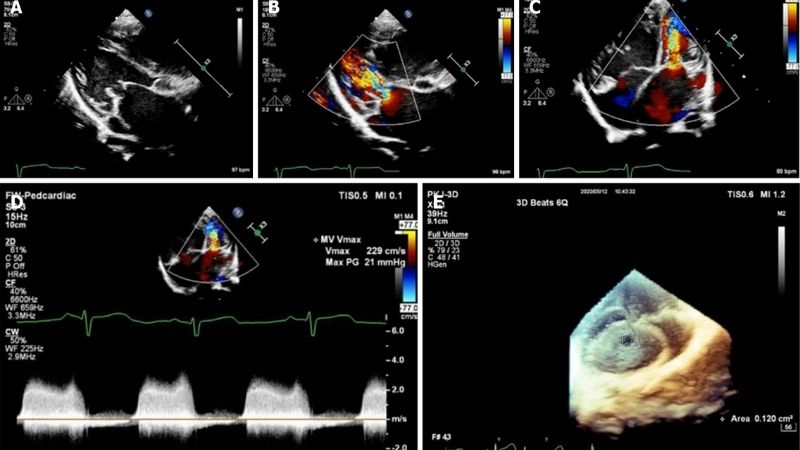

Shone's Complex is a rare congenital heart defect affecting the left side of the heart, often involving multiple obstructive lesions that impair normal blood flow.

Subaortic stenosis severe narrowing beneath the aortic valve